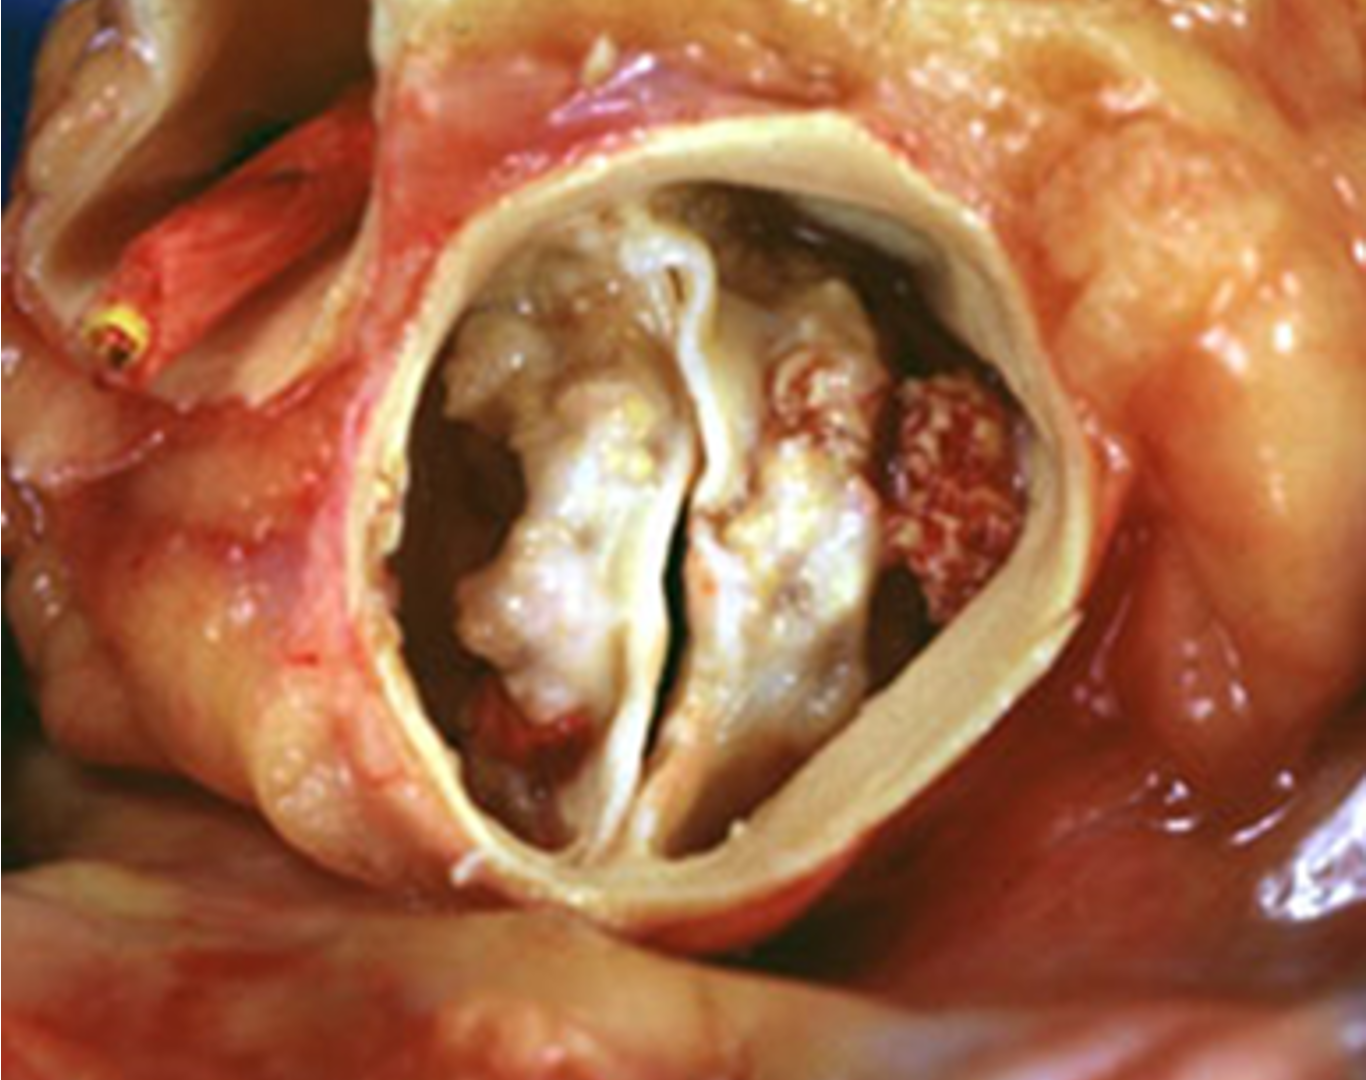

- Aortic valve sclerosis: C st. Normal tips. ↑ with age ~ atherosclerosis

- Bicuspid aortic valve (BAV): Fusion leaflets in utero. C: males (3:1). Dystrophic calcification and degeneration. Associated with A coarctation, root dilation & A dissection. Symptoms of AS: earlier than in regular aortic valve calcification.

Calcification and narrowing of the AV. Increased mean aortic pressure gradient and transvalvular velocity. Signs of cardiac remodeling, e.g., concentric hypertrophy.

Calcification and narrowing of the AV. Increased mean aortic pressure gradient and transvalvular velocity. Signs of cardiac remodeling, e.g., concentric hypertrophy.